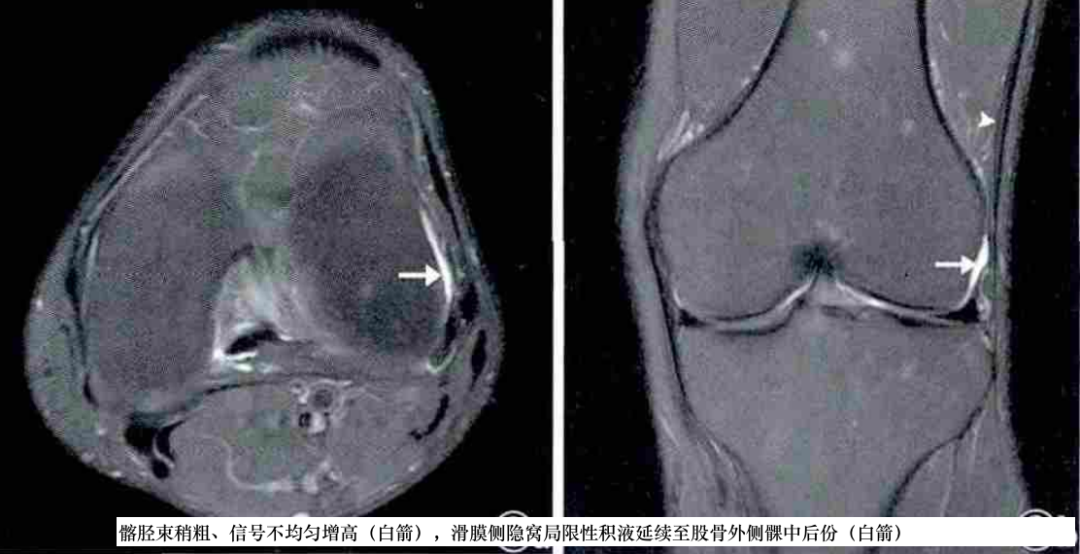

①股骨外侧髁侧方、近侧或远侧的境界不清的异常信号;②髂胫束表面或深部异常信号;③髂胫束与股骨外侧髁侧方、近侧或远侧之间局限性积液;④髂胫束位于股骨外髁水平的部分增厚、呈波浪状或连续性中断,常伴有胫骨Gerdy结节撕脱骨折和髂胫束附着处水肿;⑤关节腔积液;⑥其他异常(如半月板撕裂),其中1~3最具特征性。